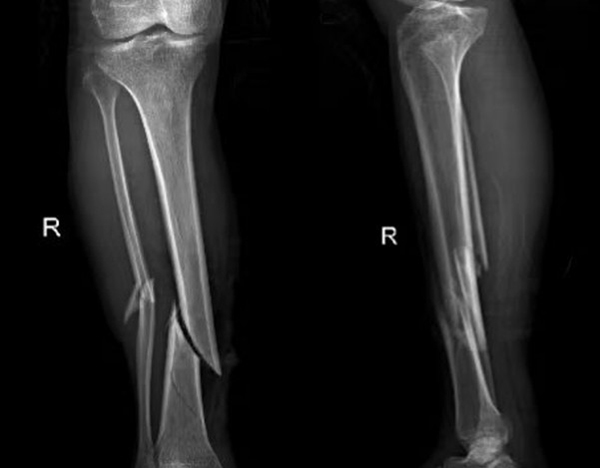

比如外伤患者,排查有无四肢骨折,X光片是首选,因为它能快速清晰显示骨骼的连续性;而检查关节内的软组织(如韧带、半月板),则需要靠MRI,CT对此几乎“无能为力”。所以,别主动要求“升级”检查,听从医生的专业建议,才能既准确又高效。